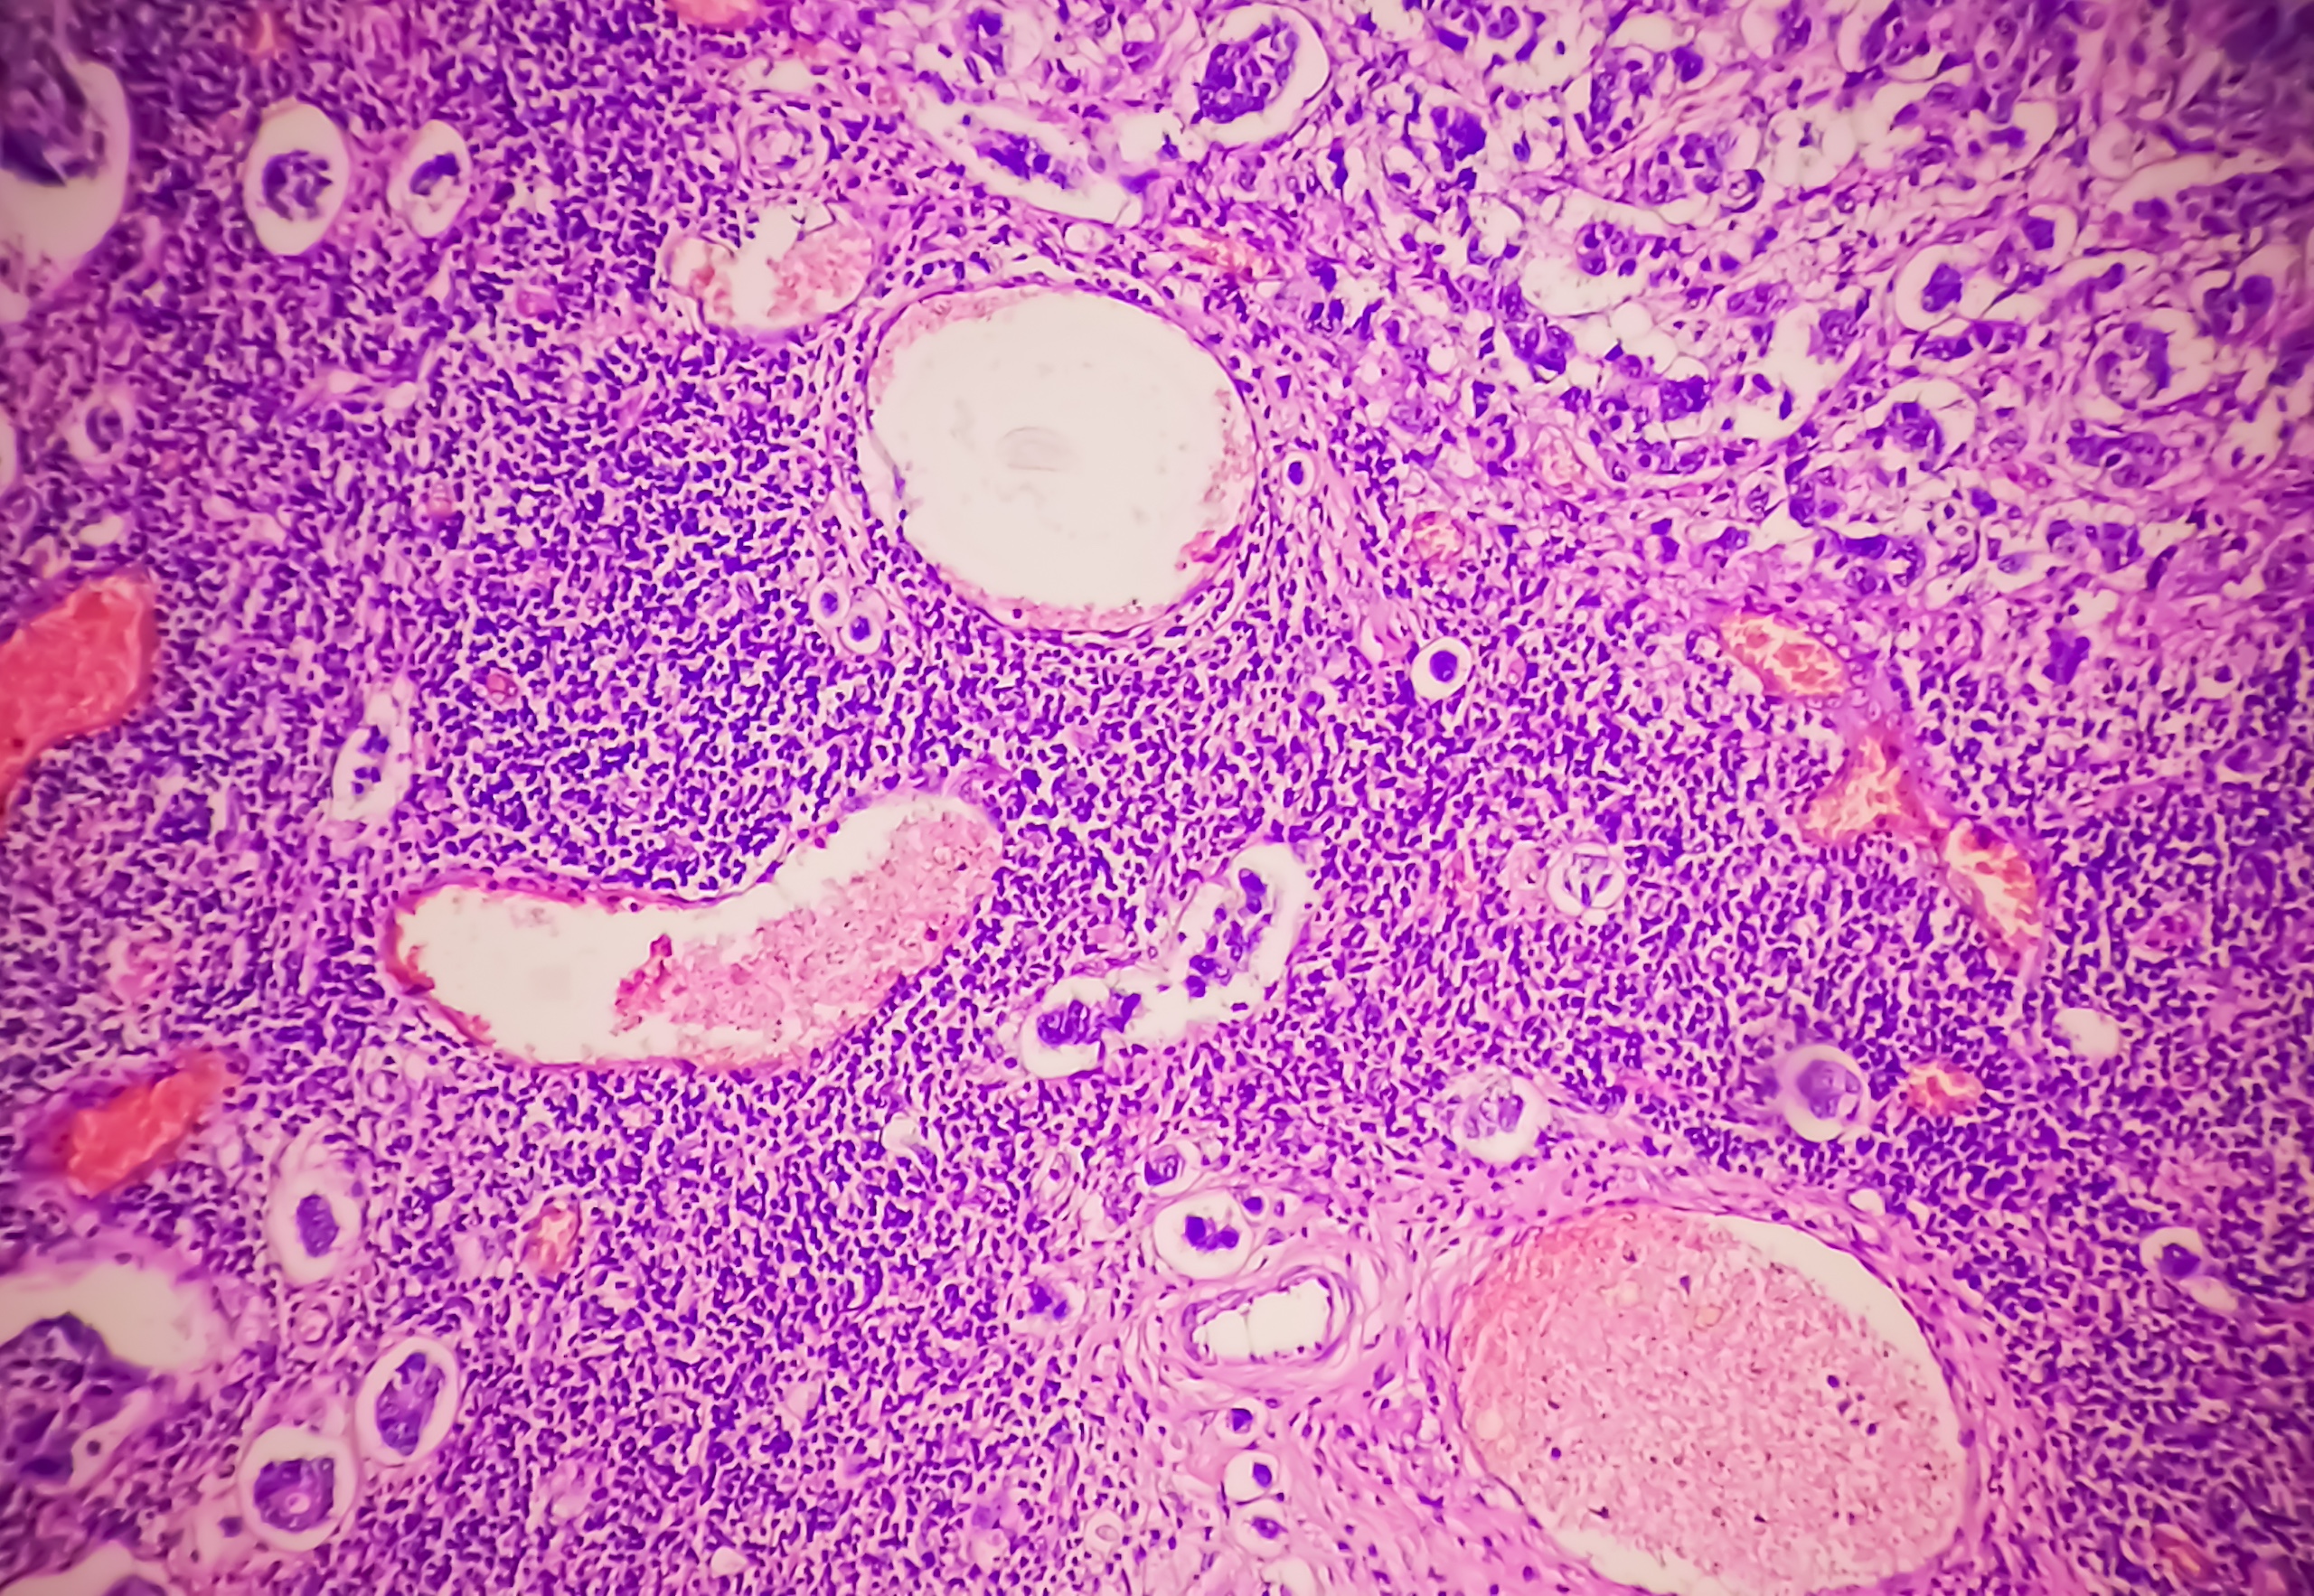

Pathology with Accessible Expertise

We foster strong partnerships with physicians and clinicians, ensuring seamless collaboration and timely support. This proactive approach enhances patient care by bridging the gap between laboratory and clinical practice, ensuring accurate and prompt medical evaluations.